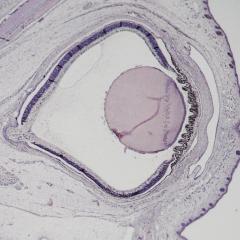

Zygote Whole Embryo

Whole Embryo Forelimb